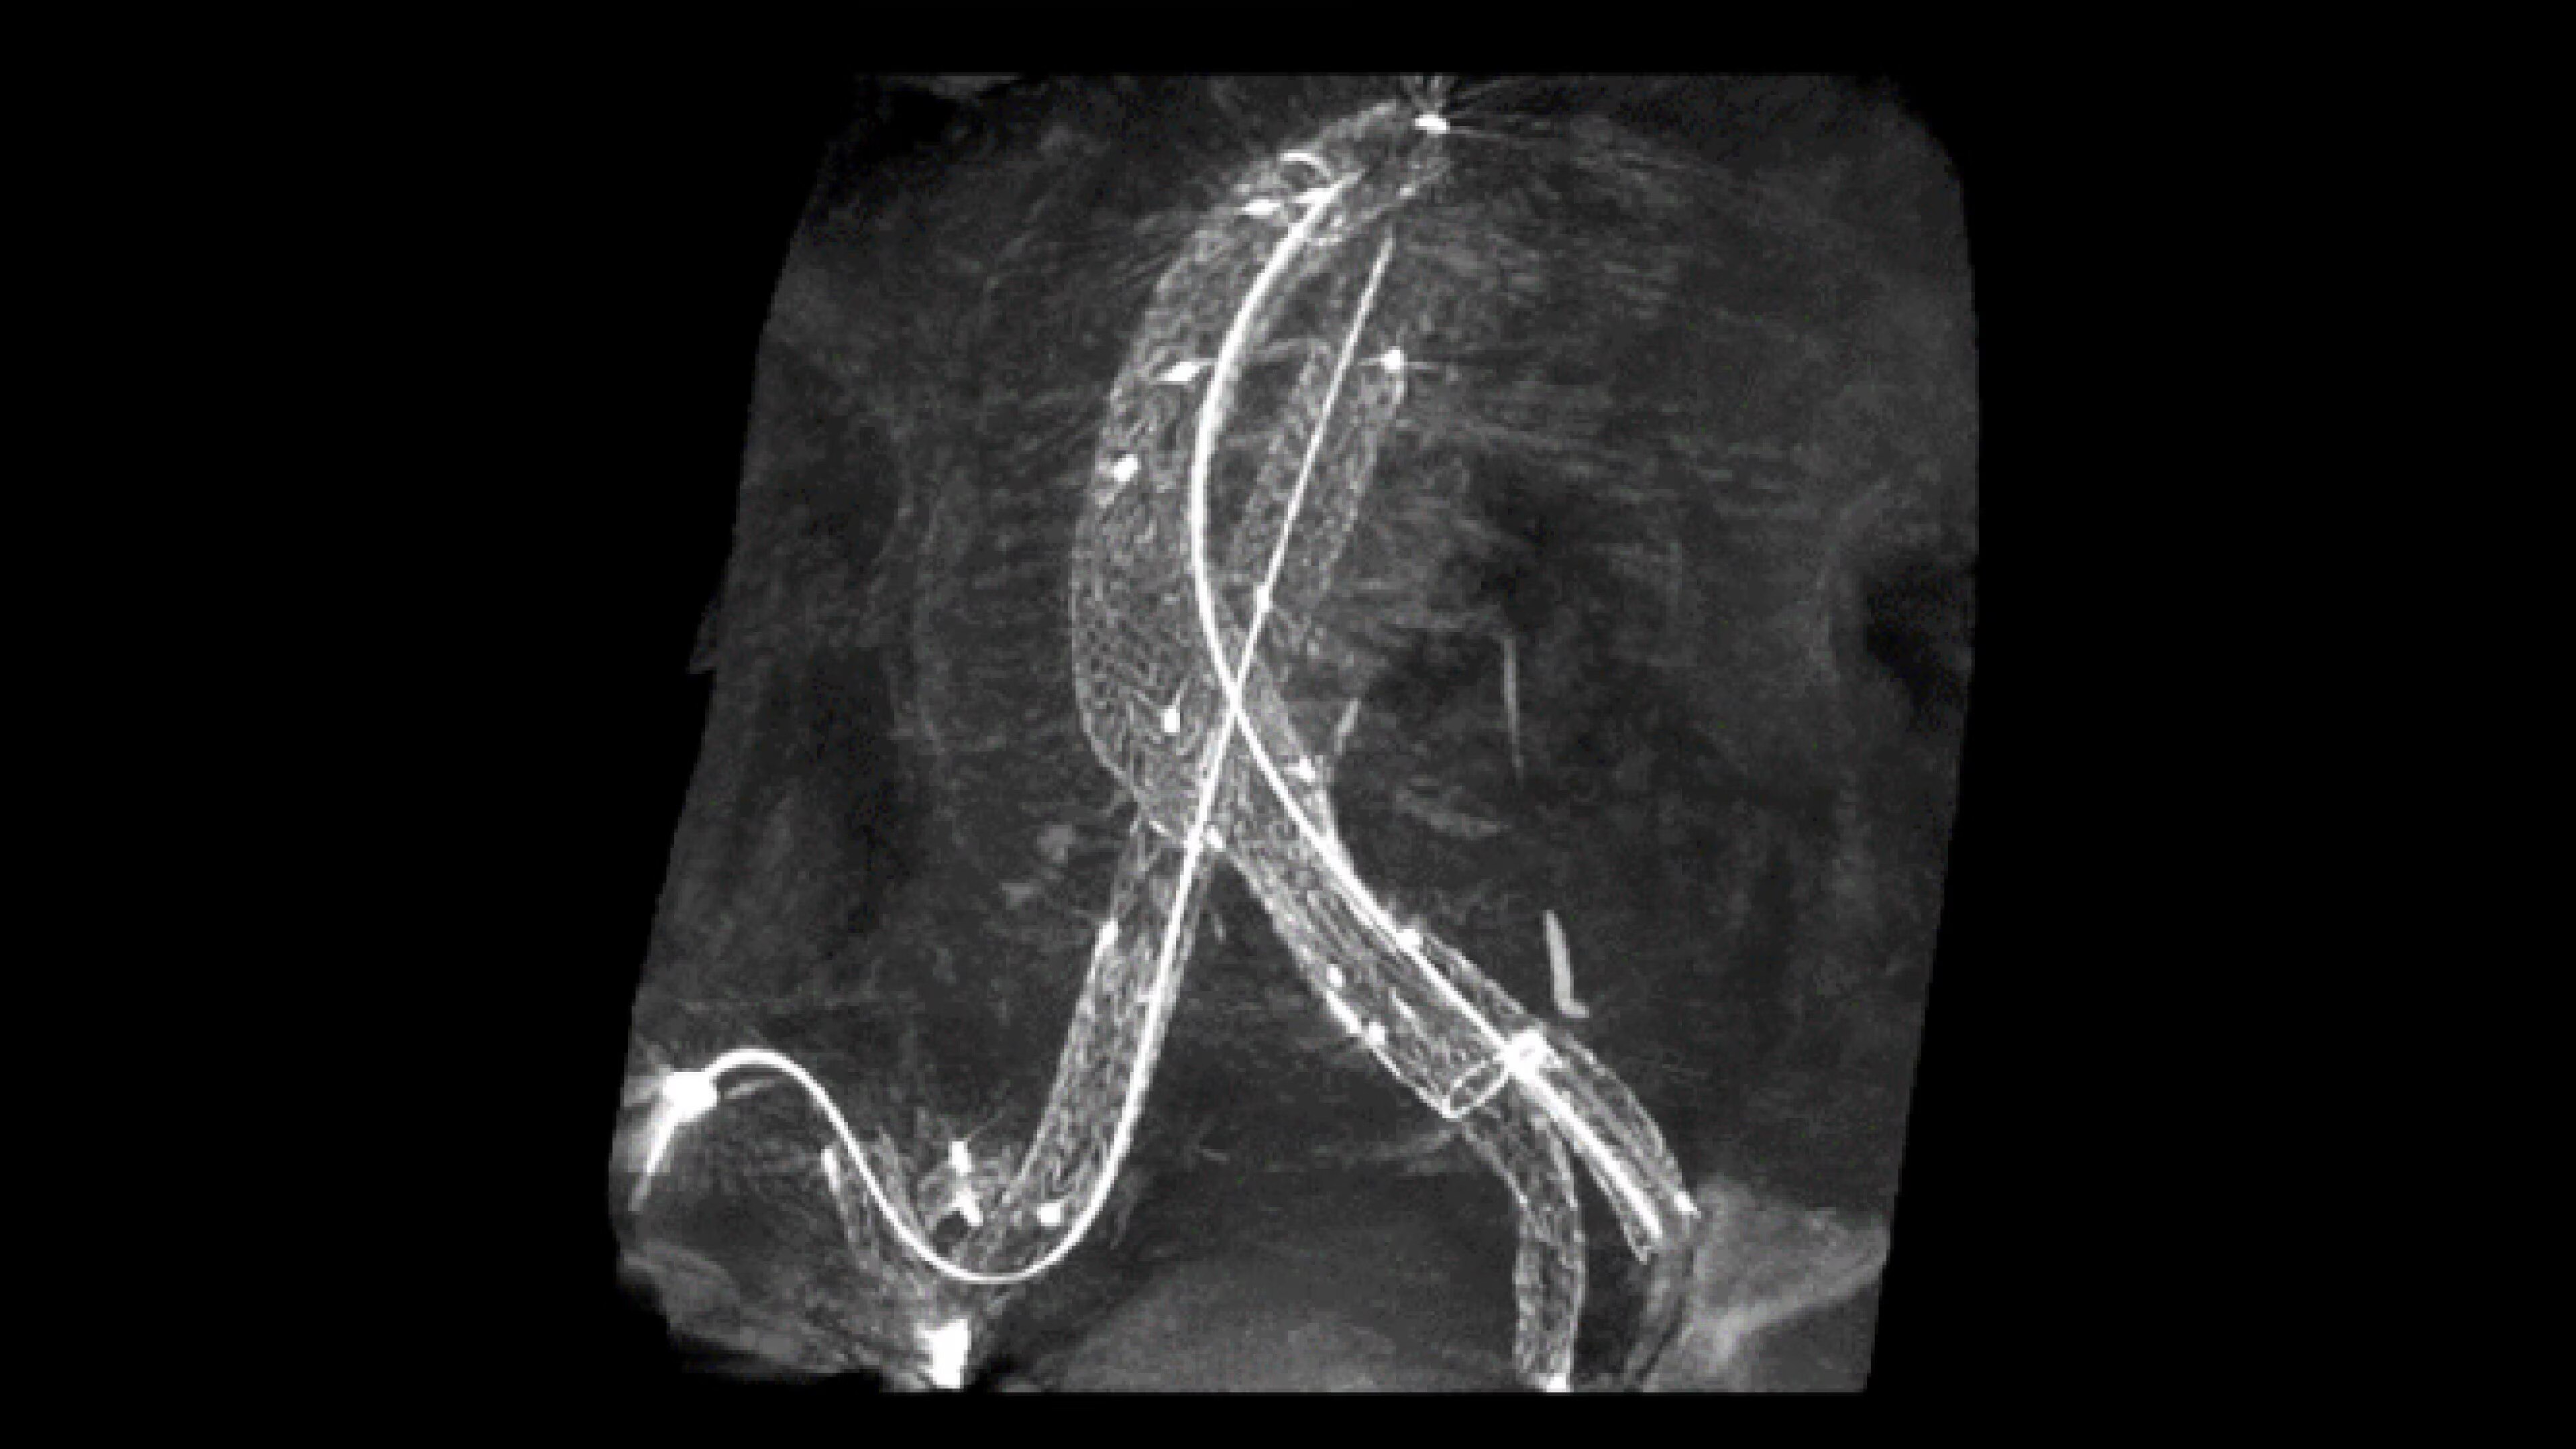

When visual confirmation during a procedure is desired, the

OEC 3D can provide 3D volumes with five perspectives.

Analyze CT-like images with the OEC 3D Volume Viewer which includes Multi-Oblique, Area Measure, Window Level/Window Width, rotate, zoom, and more for quick and comprehensive visualization.